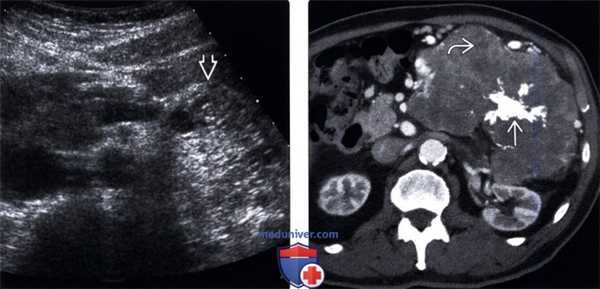

(Левый) На поперечном УЗ срезе брюшной полости в хвосте поджелудочной железы определяется гетерогенное гиперэхогенное образование с нечеткими контурами, являющееся источником интенсивных отраженных накладывающихся друг на друга акустических сигналов от множества мелких трудноразличимых кист.

(Правый) При КТ с контрастным усилением на аксиальной томограмме в теле и хвосте поджелудочной железы визуализируется крупная дольчатая серозная цистаденома с низким коэффициентом ослабления, состоящая из мелких кистозных пространств и содержащая плотный звездчатой формы кальцинат центрального рубца.